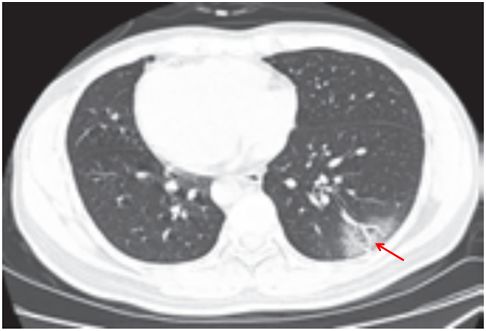

(五)结节伴晕征

部分案例实性结节病灶周围出现磨玻璃密度影,边缘模糊,称为晕征。

根据既往病理学机制提示,病灶中心实变影为肺泡腔内聚集大量富细胞渗出液,显示为实性密度灶;其周围肺泡亦见渗出,包含炎症细胞、蛋白质、纤维素等,形成“膜状物”,或形成磨玻璃密度阴影(图 2-5)。

图 2-5 结节伴晕征(A和B)